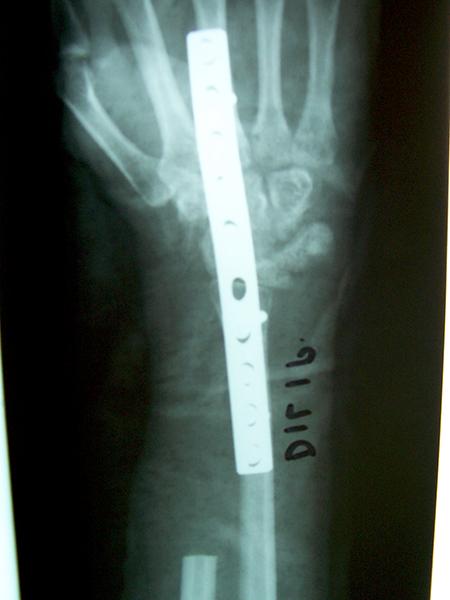

Case:2 GCT-L/E Radius

Spine Treatment In Jaipur|Best Trauma Surgeon

Pre-Op

Limb Reconstruction Doctor|Best spine surgeon

Post-Op AP

Spine Best doctor in satellite |Best Trauma Surgeon

Post-op Lateral